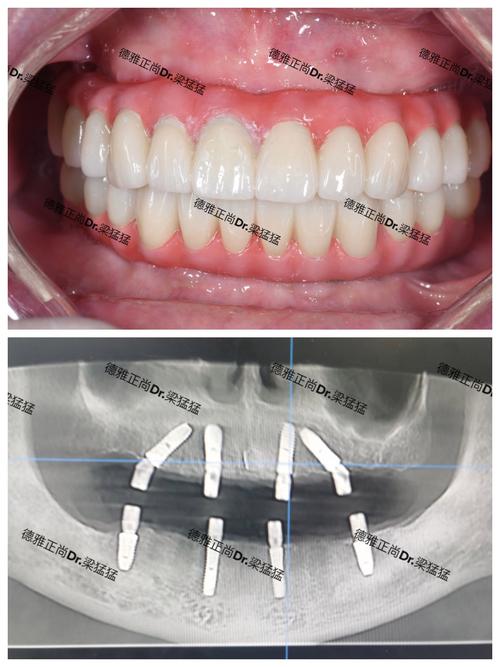

- 数字化导板: 对于复杂病例或要求高精度的病例,可能利用术前CBCT数据制作数字化手术导板,引导种植体植入,提高精度和安全性。

- 牙冠制作与安装:

- 使用数字化口内扫描仪或传统取模方式获取印模。

- 技工室根据印模和医生要求制作牙冠(基台+牙冠)。

- 试戴牙冠,检查形态、颜色、咬合关系是否合适。

- 确认无误后,永久粘固或螺丝固位在种植体上。